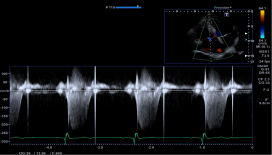

3:SWE的ECG 同步采集:显著减少了伪像,并确保了可以获得更精准的结果,

如下图所示: